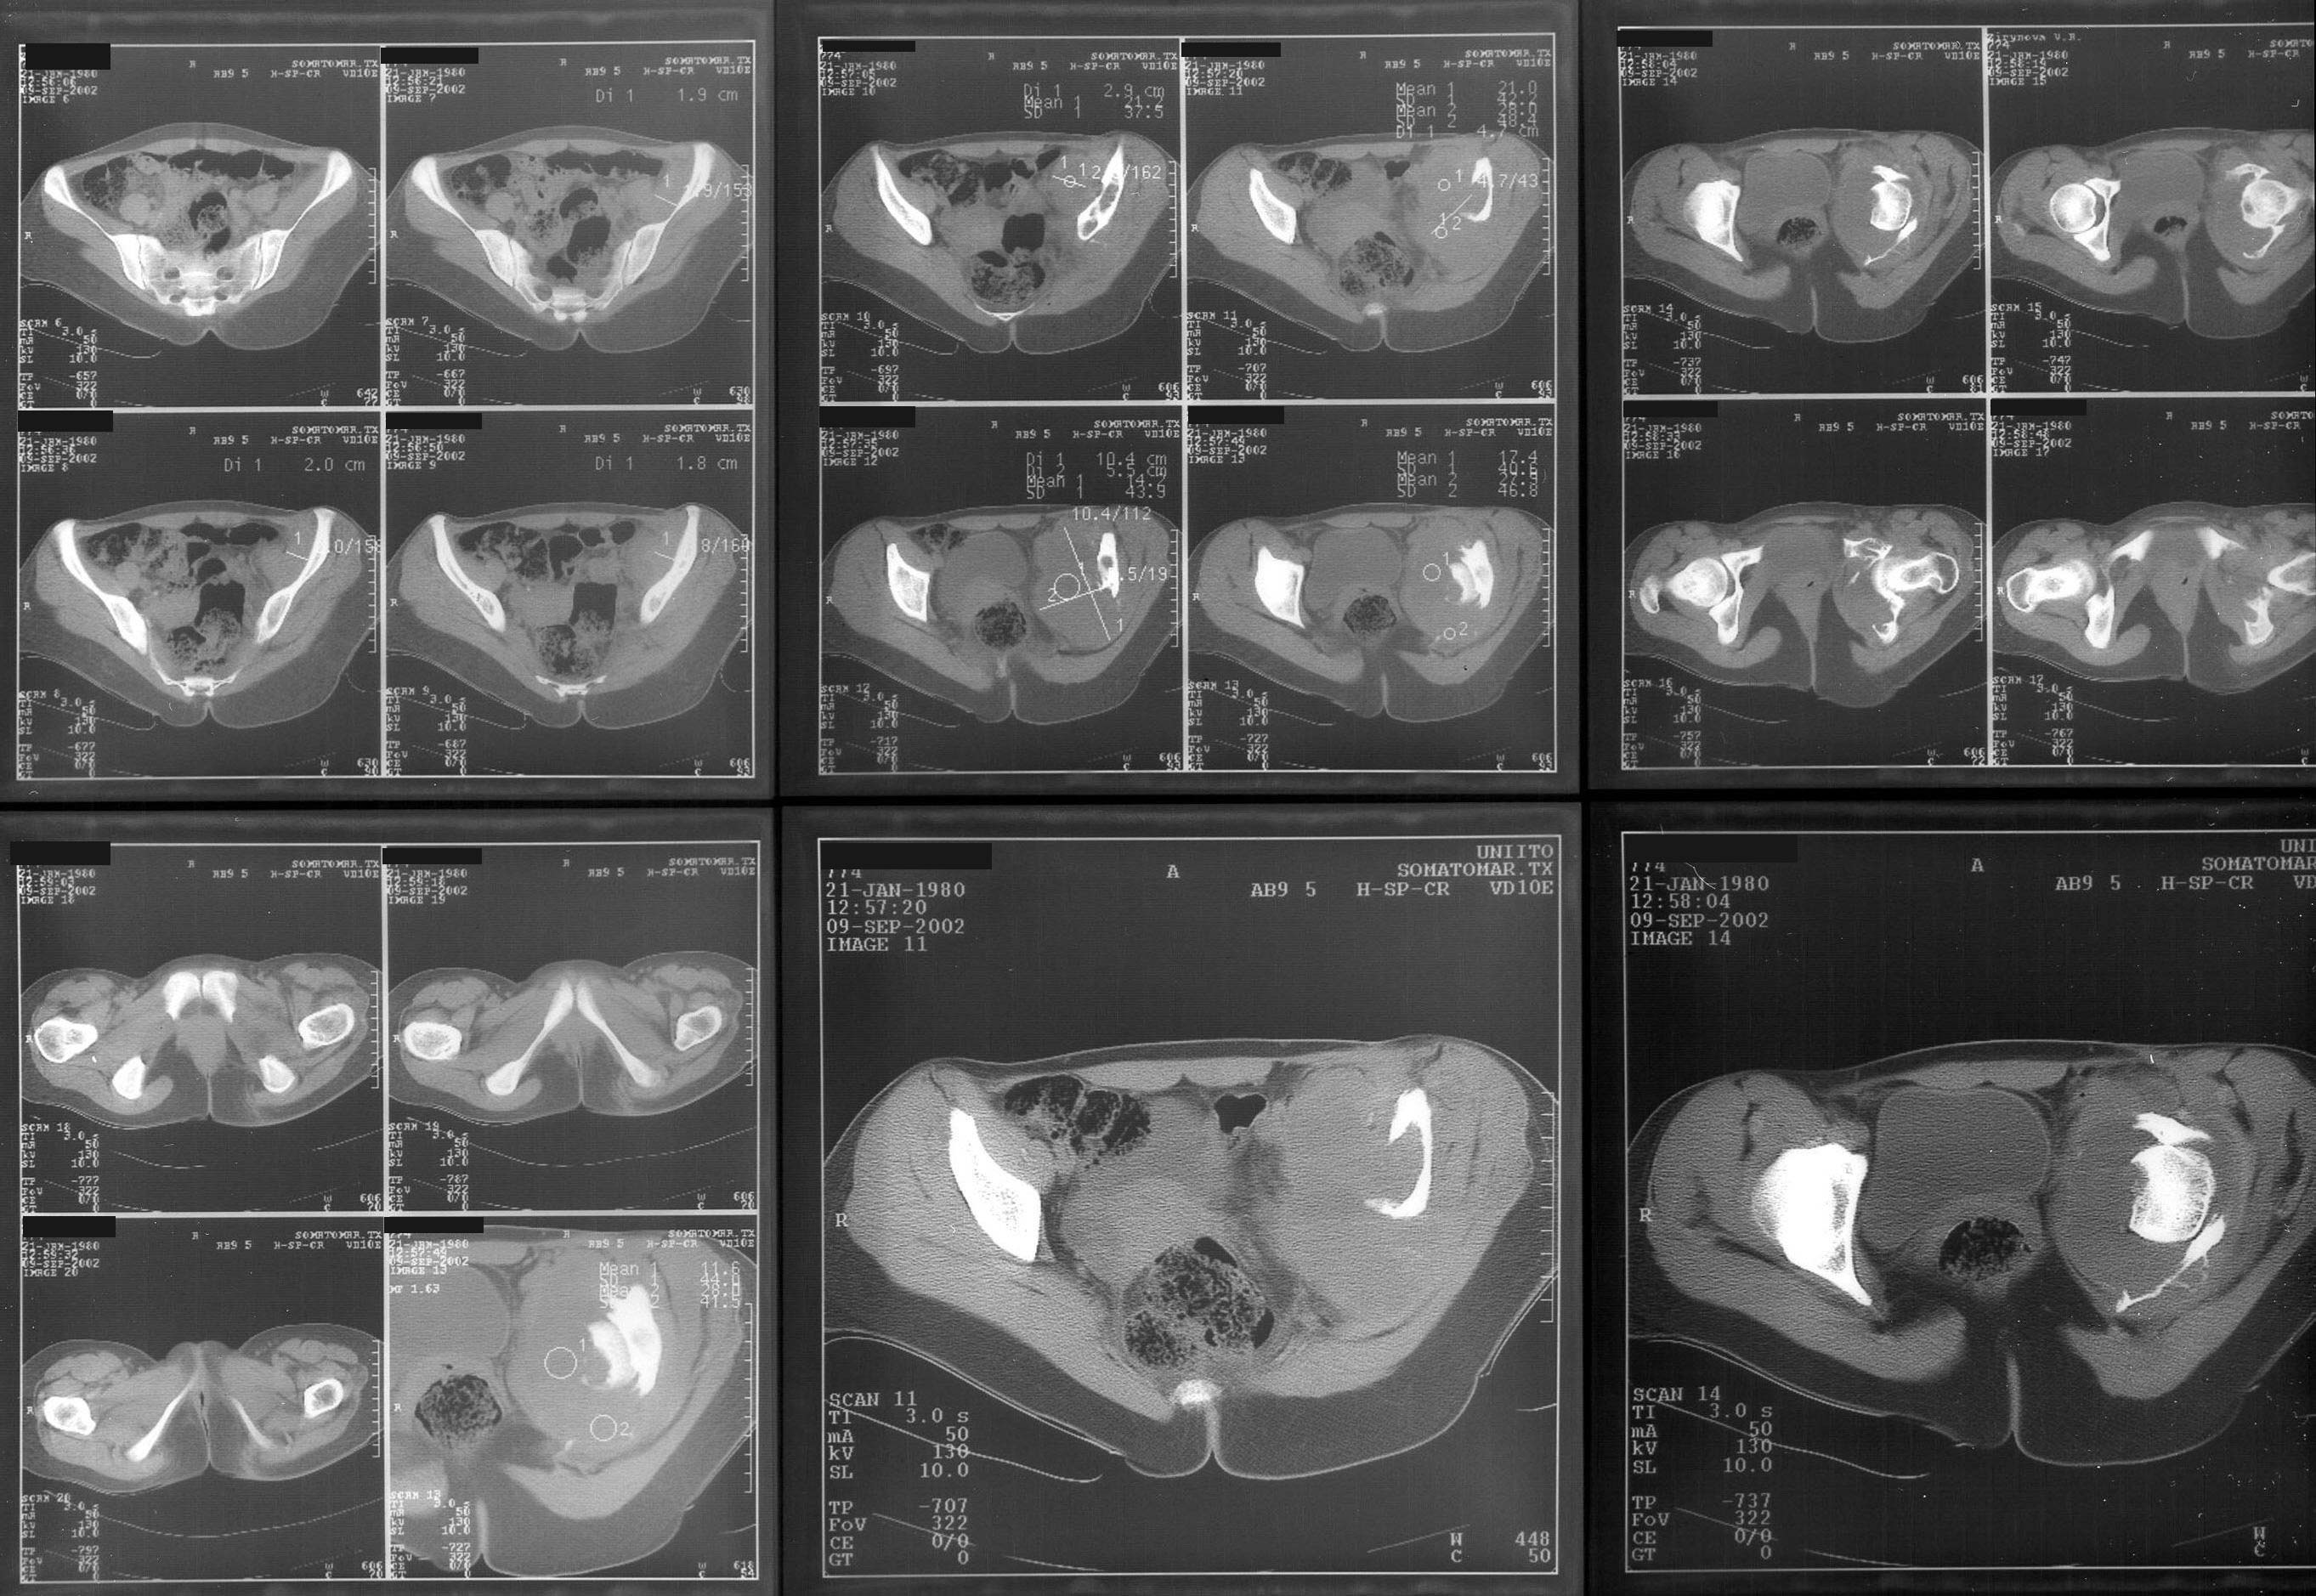

A female 22 years old admitted with the hip protrusion. Xrays are 12 months apart. Biopsy doesn't confirm malignization. What surgery can be done here? Is there any chance of primary hip replacement?

I think you need to get the opinion of a musculoskeletal oncologist, but it appears that this patient has an aggressive giant cell tumor and will likely require an aggressive wide excision. As a result reconstruction will be difficult.